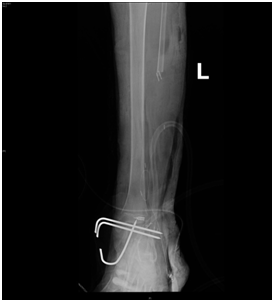

A girl, 11yearsold Saudi presented to us with progressive swelling of the left lower limb, localized above the left ankle with complaints of pain and limping gait. She had visited many clinics for her pain and swelling with no relief to her symptoms. The patient was examined clinically and there was a swelling in the lateral aspect of the distal leg tender firm too hard with intact skin over it, 4x3 cm, no other systemic clinical finding of note. X-ray of the left leg (Figure 1) showed aggressive lytic lesion of the distal fibula. Thence patient was investigated with basic lab works plus systemic and local staging for further diagnosis. She was admitted under us in pediatric surgical ward for open biopsy of the distal fibular lesion and CT of the lower limb (Figure 2) showed destructive bone lesion involving the distal end of the fibula associated with extensive destruction and aggressive periosteal reaction associated with large soft tissue mass 4.5 x 5 cm in maximum axial dimension. Also, MRI of the lower limb (Figure 3) showed there is a large destructive bone lesion involving the distal diaphysis of the left fibula. This lesion does not cross the growth plate. It is associated with aggressive periosteal reaction along with a large soft tissue mass that appears of high signal intensity in T2 and intermediate to low signal intensity in T1 sequences. This was followed by technetium-99m MDP scintigraphy (Figure 4), it showed an increased tracer uptake in the distal left fibula, extending to the left ankle and the left foot. Excisional biopsy was taken from the proximal and distal margin of the lesion in the left fibula which confirmed Ewing's Sarcoma. According to the histopathology department, they reported that there is no evidence of residual tumor i.e free resection margins. (Figure 5) The patient was referred from us to pediatric oncology clinic for further evaluation. She was electively admitted to the hospital for staging and central line insertion to start chemotherapy. She treated as per Ewing sarcoma protocol in our hospital. Patient was put on neoadjuvant chemotherapy which included vincristine, cyclophosphamide, doxorubicin and etoposide, and if osfamide 3 times weekly. After 6 months of chemotherapy, we recommend to her family to do a surgery. We did a wide surgical resection of the tumor in the left leg. Subcutaneous tissue was dissected and isolation of superficial peroneal nerve was done. Dissection of lateral compartment of the left leg up to 16cm proximal to the lateral malleolus and distally, until the distal physis (Figure 6). The tendons of the peroneus longus, peroneus brevis, and flexor halluces longus were sacrificed and the ruminants were used to reconstruct for the lateral aspect of the left ankle using suture anchors (Figure 7). K-wires were used to do temporary arthrodesis (Figure 8). The surgical wound was closed in layers. VAC dressing was also applied as standard care management in Oncology cases at KFMC and backs lab was applied (Figure 9). The last MRI done for the patient showed there is altered signal intensity of the soft tissue with post-contrast enhancement. However, the dimensions of this area of altered signal intensity are decreased as compared to previous MRI. There is no evidence of soft tissue mass lesion (Figure 10). According to the last patient's follow up after six months post-operation it shows no Valgus deviation, normal ankle motion, mobilizing full weight bearing with splint assistant during physical examination (Figure 11). Also, X-rays and MRI finding shows no residual mass lesion or local recurrence.

Figure 7 Anteroposterior ( A ) and lateral views ( B ) of plain X-ray of the left leg showed the tendons of the peroneus longus, peroneus brevis ,and flexor hallucis longus were cut and they were used to reconstruct for the lateral aspect of the left ankle using suture anchors.